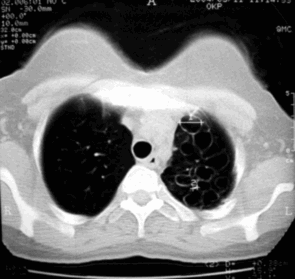

В начало Архив Компьютерные томограммы Кистозная гипоплазия легких